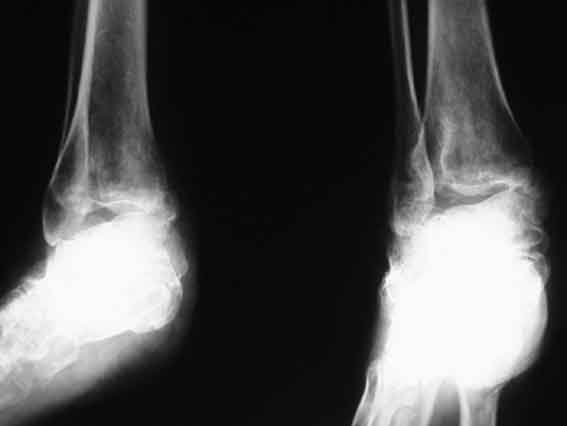

Застарелый вывих пяточной кости

Больная, 41 год, продавец, поступила в плановом порядке. Травма 1 год назад, вышла из двери второго этажа недостроенного дома с высоты 3 м. ДЗ. закр. перелом обеих лодыжек со смещением. Оскольчатый перелом пяточной кости. Вывих пяточной кости в подтаранном суставе кнаружи. При поступлении наложено вытяжение за пяточную кость 27.07 под в/в наркозом попытка устранения вывиха в подтаранном суставе (растягивался голеностопный сустав) безуспешна. Наложен гипс.

В последующем развился некроз кожного лоскута в области внутреней лодыжки 4х5 из-за натяжения кожи над внутренней лодыжкой. Консервативное лечение некроза кожи.Рана в области внутренней лодыжки зажила вторичным натяжением.В настоящее время Больная ходит на костылях с минимальной нагрузкой. При ходьбе беспокоят боли в стопе по подошве, в среднем отделе стопы, в области голеностопного сустава, переднего отдела стопы.Местно: имеется вальгусная деформация заднего отдела стопы, по внутренней поверхности стопы рубец - результат заживления раны вторичным натяжением, при пальпации резкая болезненность по подошвенно-внутренней поверхности стопы, движения в подтаранном суставе отсутствуют, при попытке их совершить появляется боль в проекции подтаранного сустава, сгибание разгибание в голеностопном суставе сохранены, болезненность появляется в крайних положениях сгибания-разгибания, имеются пронационные супинационные движения в голеностопном суставе.ДЗ Сросшийся со смещением перелом обеих лодыжек, подвывих книзу, сросшийся со смещением перелом пяточной кости вывих пяточной кости кнаружи.Коллеги, поделитесь мнением, что делать в такой ситуации?Снимок 1

Снимок 2